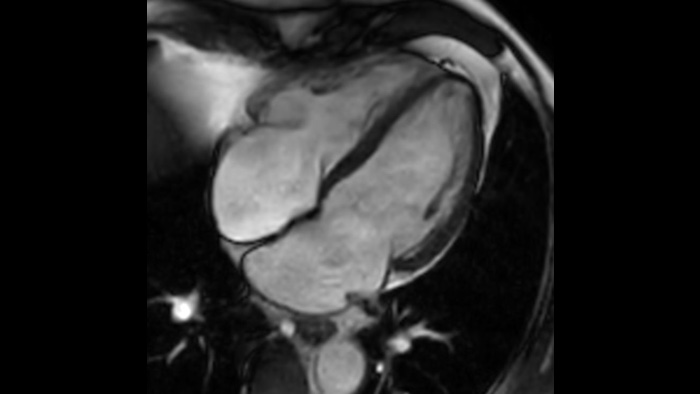

Clinical image

Diagnostic confidence

Expand your imaging capabilities in all clinical areas. See how your peers are benefiting.